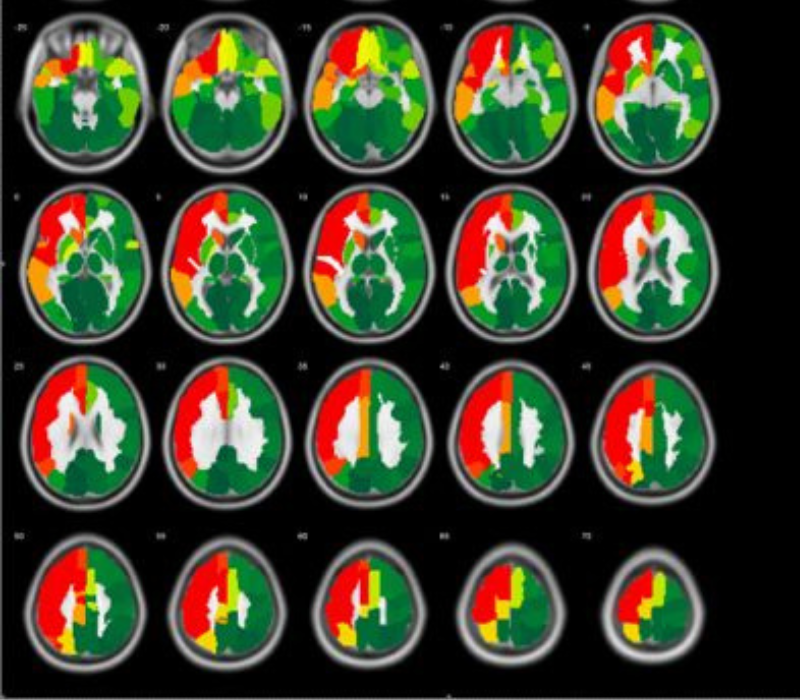

Zunächst wird bei allen Teilnehmerinnen und Teilnehmern die Duchblutung und die Krankheitsaktivität genau bestimmt. Dies geschieht mit den neuesten Methoden der Bildgebung:

Hochmoderne, von uns gemeinsam mit der Abteilung für Neuroradiologie stark weiter entwickelte Kernspintomographie in Atemanhalte-Technik

Beste verfügbare Diagnostik

Die Patientinnen und Patienten erhalten durch die Teilnahme an der Studie die aktuell beste verfügbare bildgebende Diagnostik mit MRT und Positronen-Emissions-Tomographie (PET/CT). Insbesondere das PET/CT wird häufig von den Krankenkassen nicht gezahlt. Im Rahmen dieser Studie steht den Teilnehmerinnen und Teilnehmern das PET/CT kostenfrei zur Verfügung.